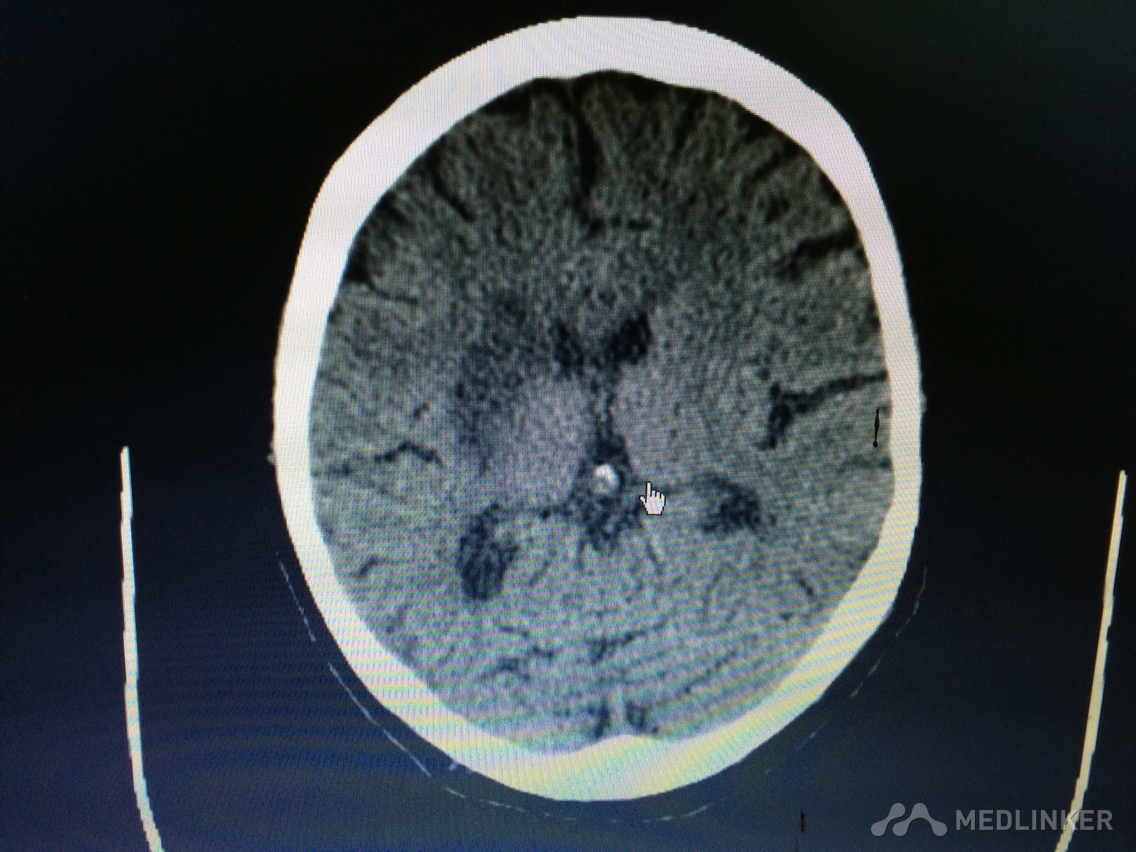

下面的CT梗塞灶,请问对应血管?